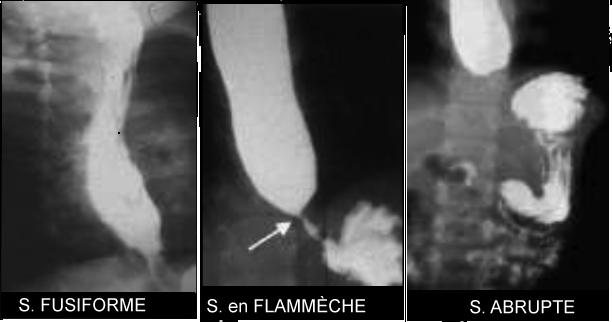

- Stenose congenitale

et anormalie de l'oesophage inferieur :

Incidence de stenose oesophagienne congenitale

pres de 1/25.000 a 1/50.000 . De 17% - 33% avaient avec

des autres malformations ( 1/3 ) . Ce qui attenir sur

les nourrisson jusqua 6 mois asymtomatiquement .Signe le

plus souvent est vomissement , disphagie ,

regurgitation, retard de croissante et syndrome de

respiratoire ( sweezing , cyanose ) . Lesion

histologique le plus souvent est epaissisement

fibromusculaire parietale , ou bien anneau cartilagineux

, parfoie valvule menbraneuse . Au point de vue

radiologique , ils y avaient 3 types de stenose

oesophgienne congenitale

| |

- Type Ia : stenose distal effilee

- Type Ib : stenose distal "abrupte

"

- Type II :

flammeche ( flash-shape shadow )

- Type III

: Comme type I , II avec extravation de

radio-opaque a hauteur de la stenose

|

Image

radiologique de deux type de stenose oesophgienne

congenitale 1a, 2 et 1b en fusiforme , en flammeche

et abrupte |